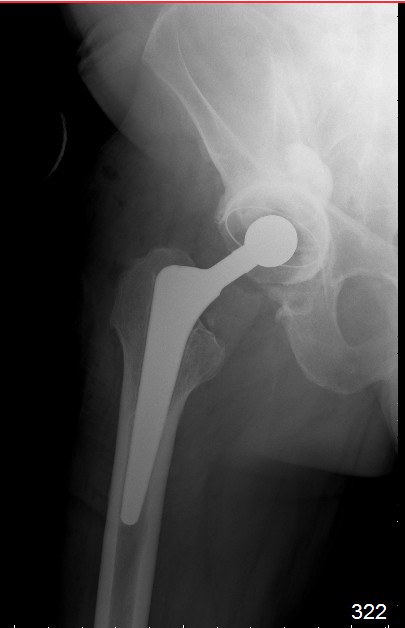

В дополнение к моему вышеуказанному пациенту. Досылаю послеоперационный снимок, который я не выслал сразу.